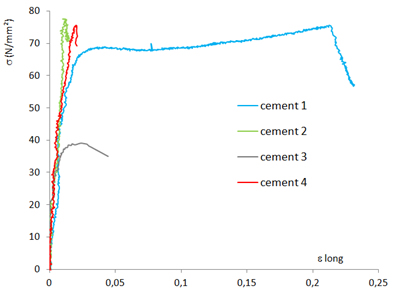

Caractérisation thermo mécanique des ciments biocompatibles

Caractérisation thermo mécanique des ciments biocompatibles